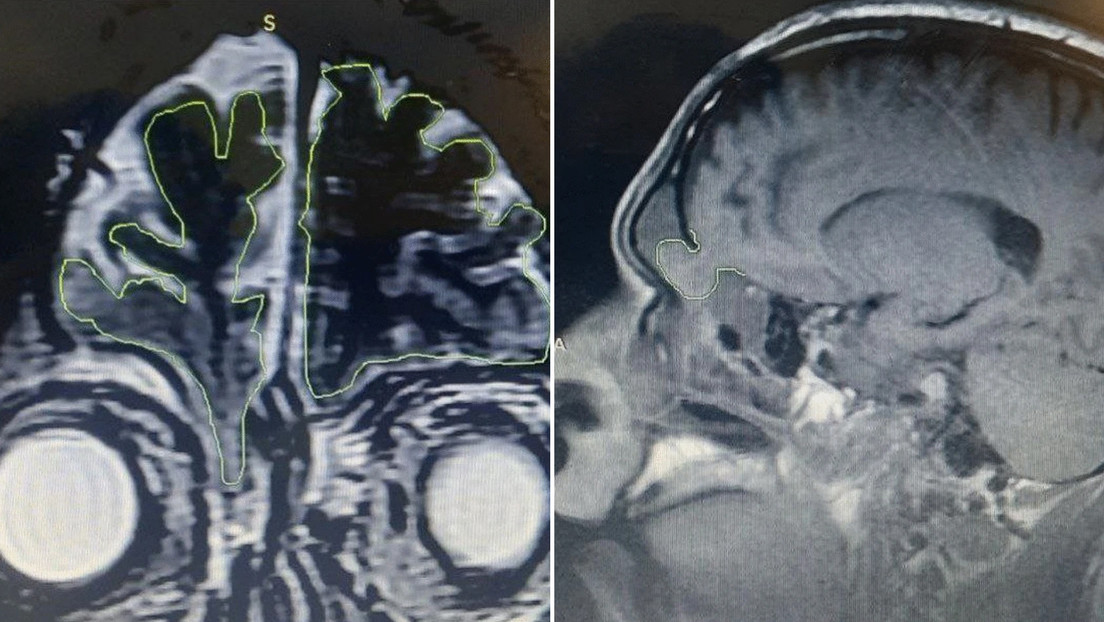

El hombre fue sometido a investigaciones radiológicas, que mostraron que tenía una fractura de base con un encefalocele, que es una afección en la que la materia del cerebro empieza a salir por orificios del cráneo, como la cavidad nasal.

En vista de las complicaciones, los médicos decidieron operarlo para devolver los tejidos cerebrales herniados a su ubicación normal, reparar las meninges y reconstruir la base del cráneo con cemento óseo y biopegamento. La intervención y la posterior recuperación del paciente no tuvo complicaciones y recibió el alta hospitalaria a los dos días.